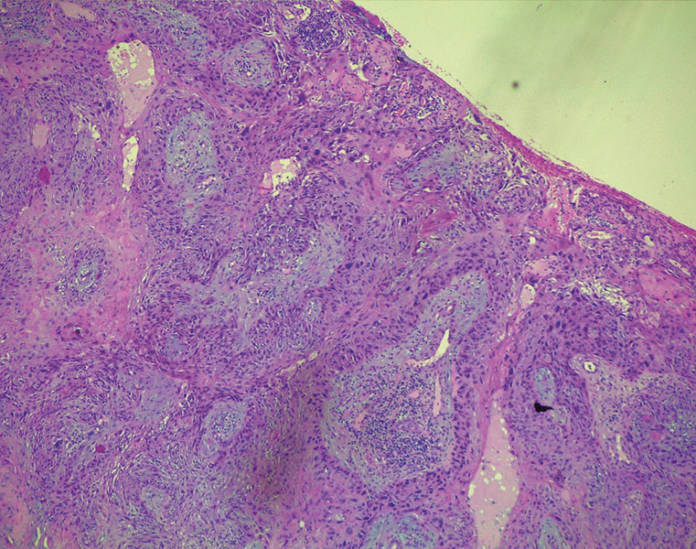

Anatomia patologica

(1,5,9,10) (tab. 2)

L’istotipo maggiormente rappresentato è il carcinoma basocellulare. Si può presentare sia come nodulo che come formazione ulcero-nodulare o come ulcera con margini duri. Tale tumore, benché sia maligno, non ha la tendenza a generare metastasi, ma se non diagnosticato e trattato in tempo tende a erodere e infiltrare i tessuti e le strutture circostanti e profonde.

Il secondo istotipo quanto a incidenza è il carcinoma spinocellulare. Si presenta, il più delle volte, con la comparsa di noduli duri o placche. Oltre ai fattori di rischio già citati, questo istotipo è spesso correlato a un’infezione da HPV. Il gold standard è la terapia chirurgica; nei casi ad alto rischio si associa la biopsia del linfonodo sentinella; nel caso in cui lo stesso risulti invaso c’è indicazione sia alla chemio che alla radioterapia (10).